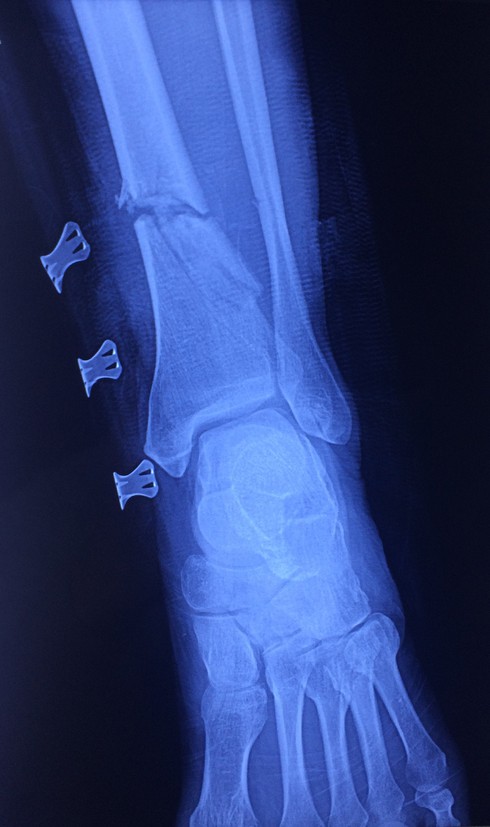

Hình ảnh trên phim xquang của bệnh nhân. |

Ngày 31/12/2019, Bệnh viện Hữu nghị Việt Đức tiếp nhận trường hợp người bệnh B.V.L (56 tuổi, Hòa Bình) nhập viện trong tình trạng vết thương hở đứt 3/4 chu vi cẳng chân trái, chảy nhiều máu; mất vận động cổ chân và các ngón chân, gãy hở xương chày, đứt hoàn toàn các gân cơ khu trước và sau cẳng chân, đứt bó mạch chày sau, chày trước.